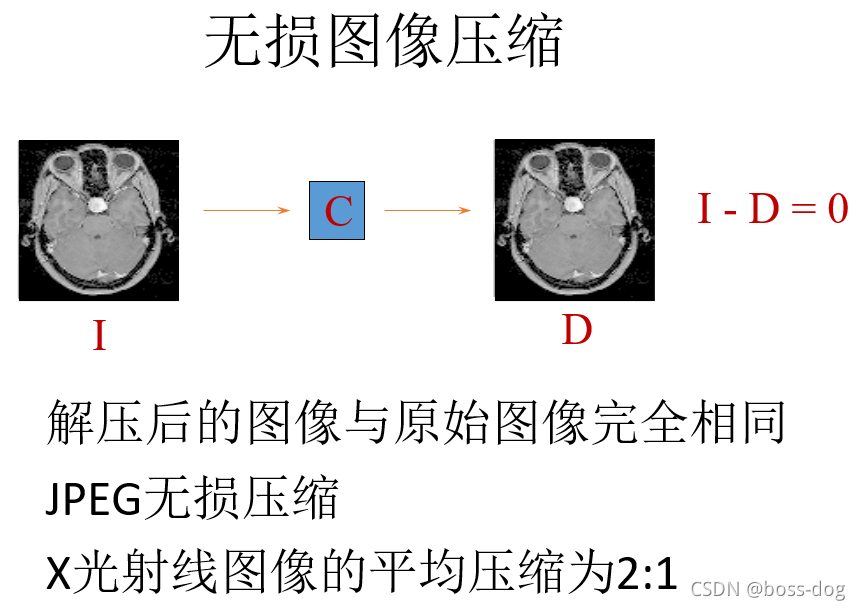

JPEG 2000 符合无损压缩。